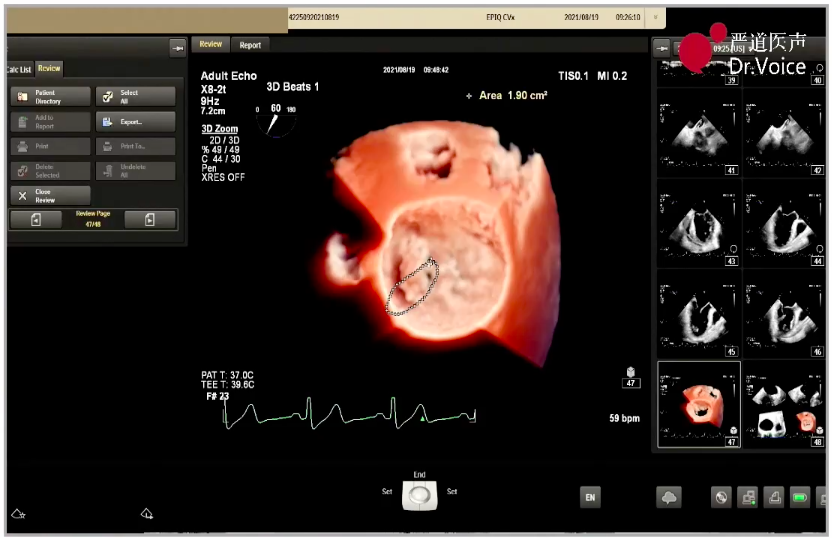

1、手术团队使用MitraClip®独特的三层双调弯导管,经股静脉穿刺,在食道超声引导下完成房间隔穿刺。穿刺后将导管送入左心房,靠近二尖瓣目标位置。术中TEE三维超声可明确显示瓣膜脱垂区域,脱垂区域主要位于二尖瓣前叶A1区及前交界,且面积较大,显著增加手术难度。

三维超声显示瓣膜脱垂区域